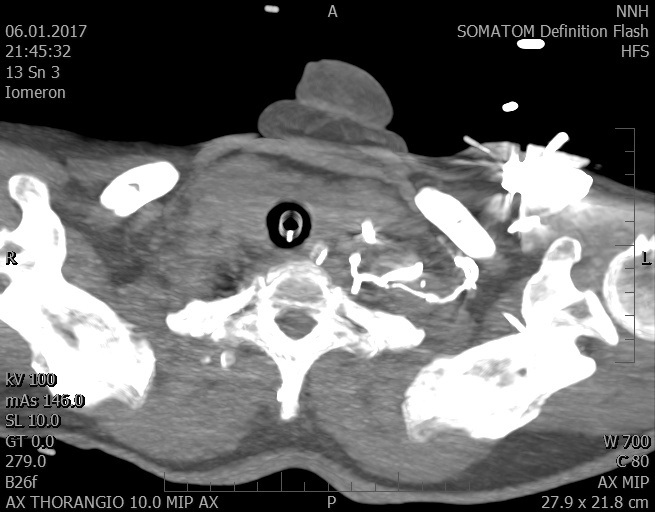

Video 1 - Akutní koronarografie prokázala normální nález na věnčitých tepnách s výjimkou suspekce na lehký spasmus na pravé koronární tepně.Echokardiograficky byla zjištěna těžká dysfunkce dilatované levé komory s nezvětšenou pravou komorou (video 2).

Video 2 - Echokardiograficky byla zjištěna těžká dysfunkce dilatační levé komory s nezvětšenou pravou komorou.Pro nejasnou příčinu zástavy jsme provedli i vyšetření výpočetní tomografií (CT), které vyloučilo plicní embolizaci (série 1 - soubory na konci článku). V den přijetí při přetrvávající oběhové nestabilitě byla nemocná opakovaně defibrilována pro fibrilaci komor se stabilizací rytmu po podání amiodaronu a mesocainu. Dle hemodynamických měření se jednalo o těžký kombinovaný šok. Vstupní laboratorní vyšetření bylo bez větších pozoruhodností. Posléze jsme doplnili anamnézu od příbuzných a zjistili, že pacientka užila do dvou hodin před srdeční zástavou první tabletu amoxicilinu na lehký respirační infekt. Při nevýtěžnosti vstupních vyšetření a nových anamnestických informacích jsme doplnili 14 hodin po kolapsu vyšetření koncentrace tryptázy v séru, která byla extrémně zvýšena (tabulka 2), což nás vedlo k podezření na anafylaxi.